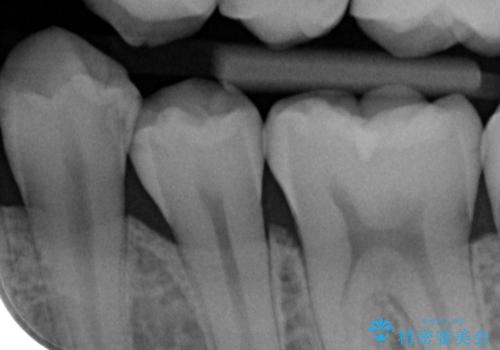

- 矯正前の患者様です。検査により虫歯がありましたのでe-maxインレー治療を行いました。

- e-maxインレー 7.7万×2費用は治療当時の料金となります